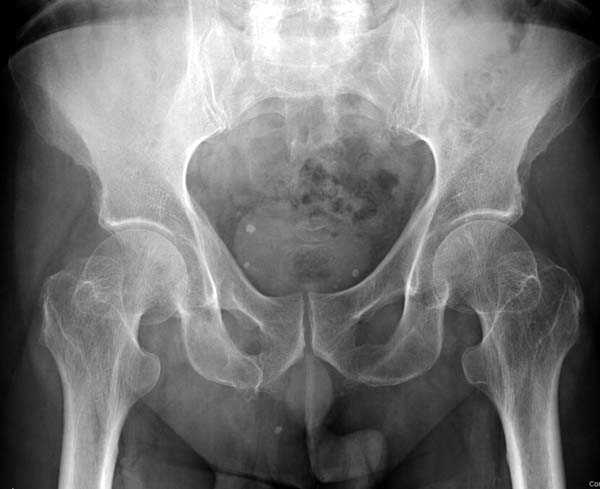

Почему неполный перелом? Я бы назвал его вколоченным!

Перелом конечно не вколоченный т.к. видно линию перелома и нет суперпозиции костной ткани.

Добрый день. Перелом коварный. Через время может произойти лизис в области "неполного" перелома и он превратиться в "полный" со всеми очевидными проблемами, тем более у пациента, склонного к питию. Если не разовьется делирий или после выхода из него, рекомендую внутренний остеосинтез винтами.

На второй день после выписки упал дома. Снимки приложены. Коллеги рекомендуют удаление шурупа и вытяжение. Что делать?